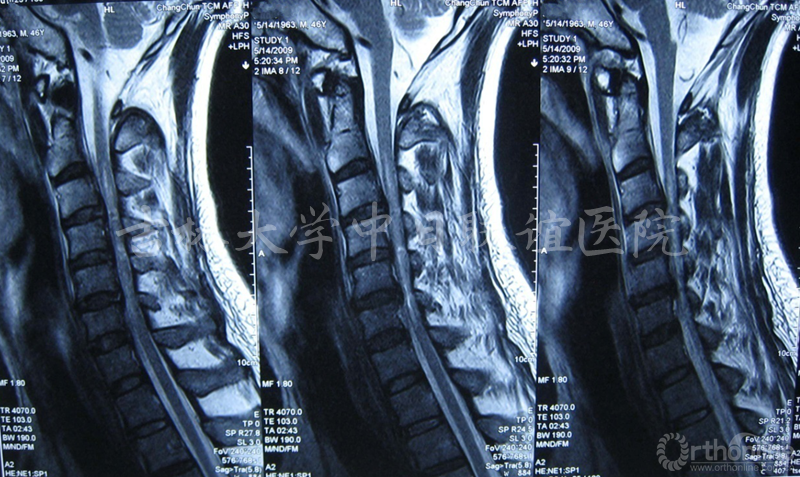

男性患者,诊断为“发育性椎管狭窄伴无骨折脱位型颈脊髓损伤”,行C3-6后路双开门椎管扩大成形术。

患者术前术后影像学资料